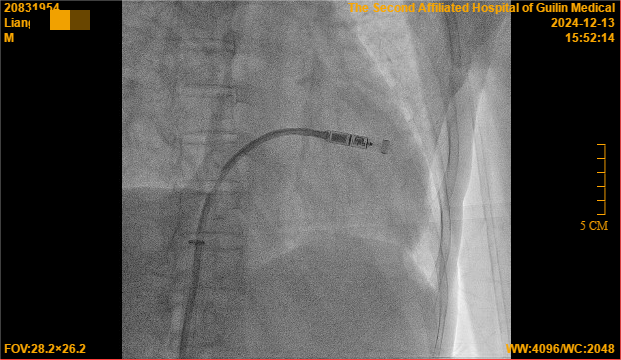

12月13日,心血管内科二病区团队通过局部麻醉方式为梁大爷进行了无导线起搏器的植入手术,用时仅45分钟,手术体验良好,几乎无痛感,让怕痛的梁大爷啧啧称赞,起搏器头端的“抓捕器”(电极)精准定位,一次性抓捕到合适的心肌,测试各项起搏参数均非常理想,术后仅有一个小穿刺口,局部加压止血即可。